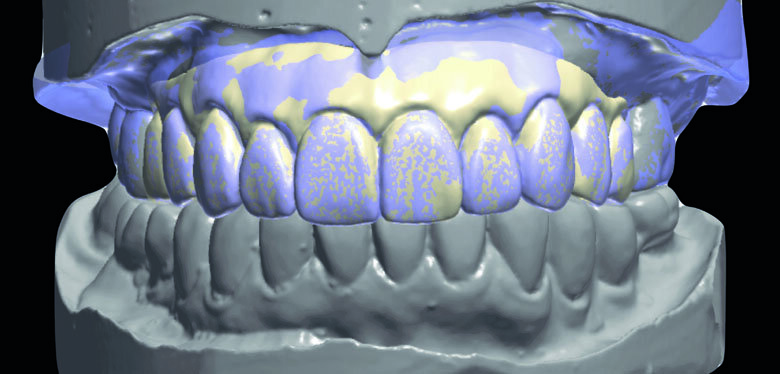

Fig 9. Prepared cast and Diagnostic cast were scanned and transformed into STL file.

Fig 10. Two sets of STL data were super-imposed and sent for milling.

Preparation cast with a diagnostic wax-up ca st was sent to a local laboratory for scanning and transforming into STL (Stereolithography) digital impression file. (Fig 8,9.) Two sets of STL impressions were super-imposed in the software in order to subtract the overlapping data. This process was done in order to transform the diagnostic wax-up into the STL digital impression. Consequently, the STL data was sent to the laboratory for milling. (Fig10.) A monochromatic milled-PMMA temporary bridge was fabricated in a local laboratory and returned to the dentist for composite layering. (Fig 11.) Gingival cutback was made to create sufficient gingival space for pink composite layering (Fig 12). Prior to composite layering CeraResin Bond 1 was applied and left for 10 seconds to prime the surface, followed by application of CeraResin Bond 2 for 10 seconds and light cured for 20 seconds (Fig 13.). Ceramage Indirect Composite gingival shade GUM-O (GUM Opaque) was applied to mask the color of PMMA (Fig 14.). GUM-D (GUM Dark) was applied on the attached gingiva area to the buccal flange (Fig 15.). GUM-L (GUM Light) was applied in the region of free gingiva (Fig 16.). F-GUM-R (Flowable GUM Red) and F-W (Flowable GUM White) were painted to mimic the mucogingival junction and vascular alveolar mucosa (Fig 17.) GUM-T (GUM Translucent) was applied to reproduce of reddish translucent gingiva areas (Fig 18) to achieve natural gingival aesthetics.